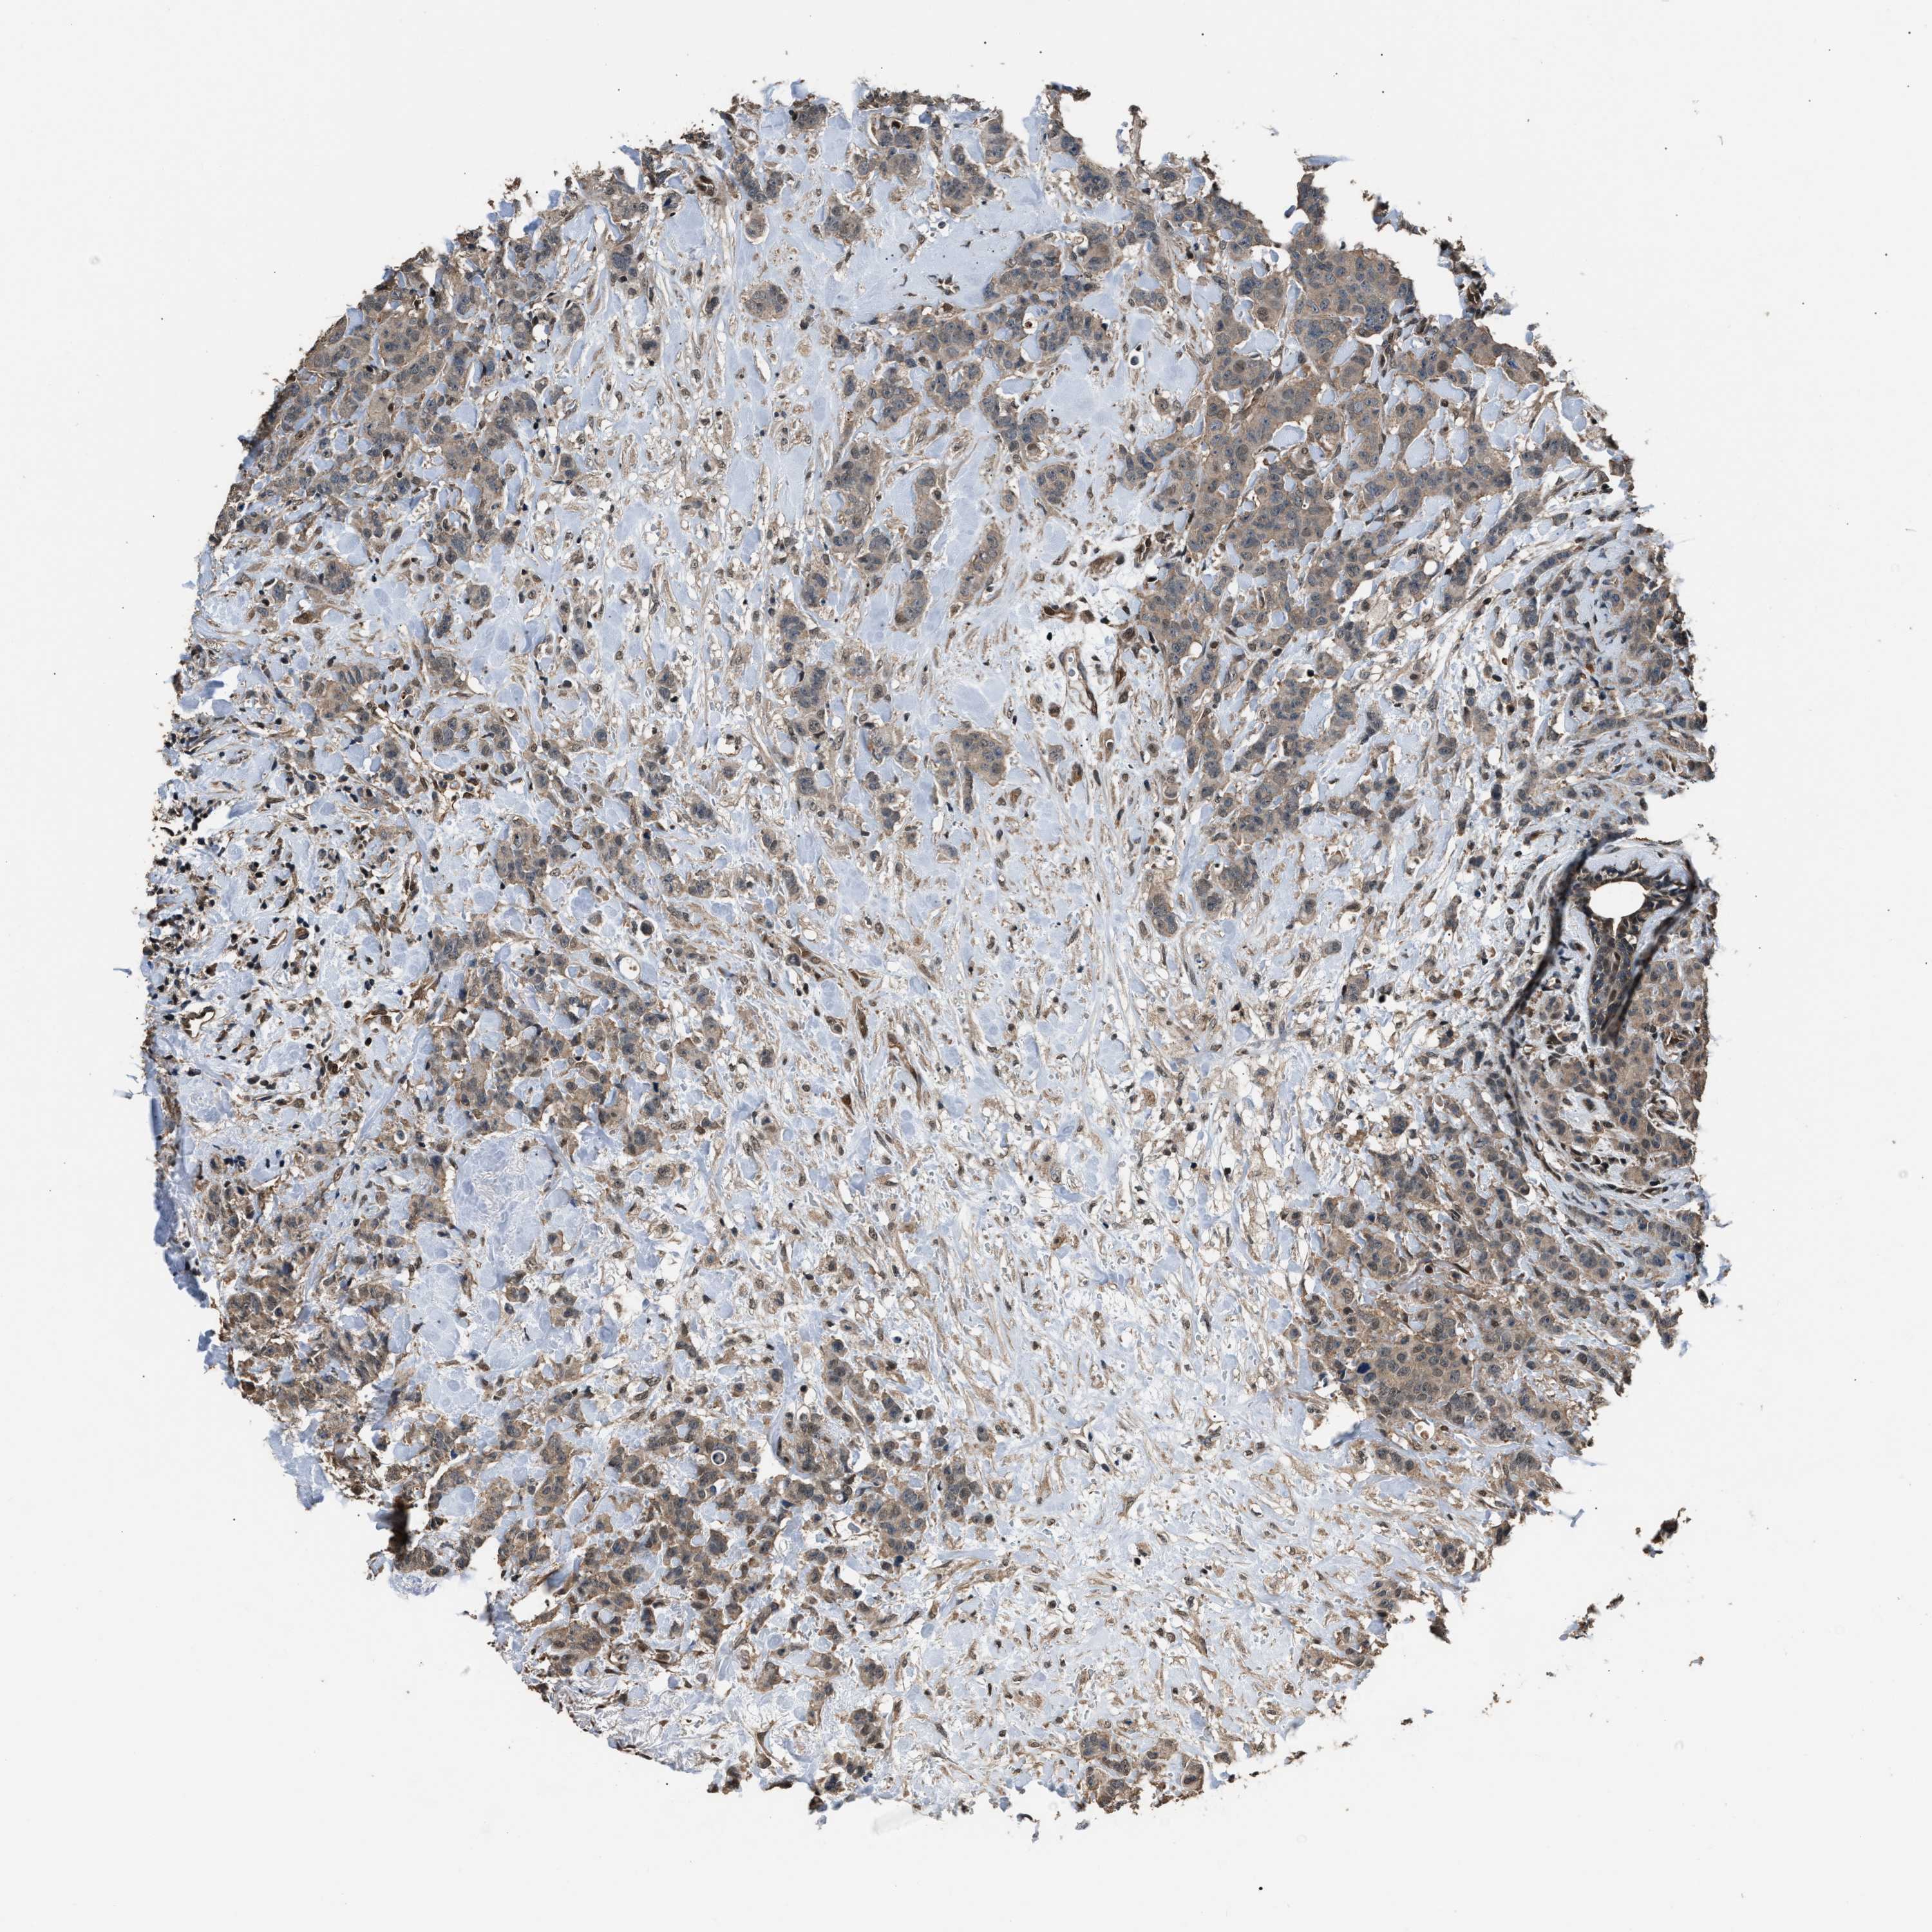

CANCER BREAST CANCER Show tissue menu

BRCA TCGA BRCA VALIDATION PROTEIN EXPRESSION